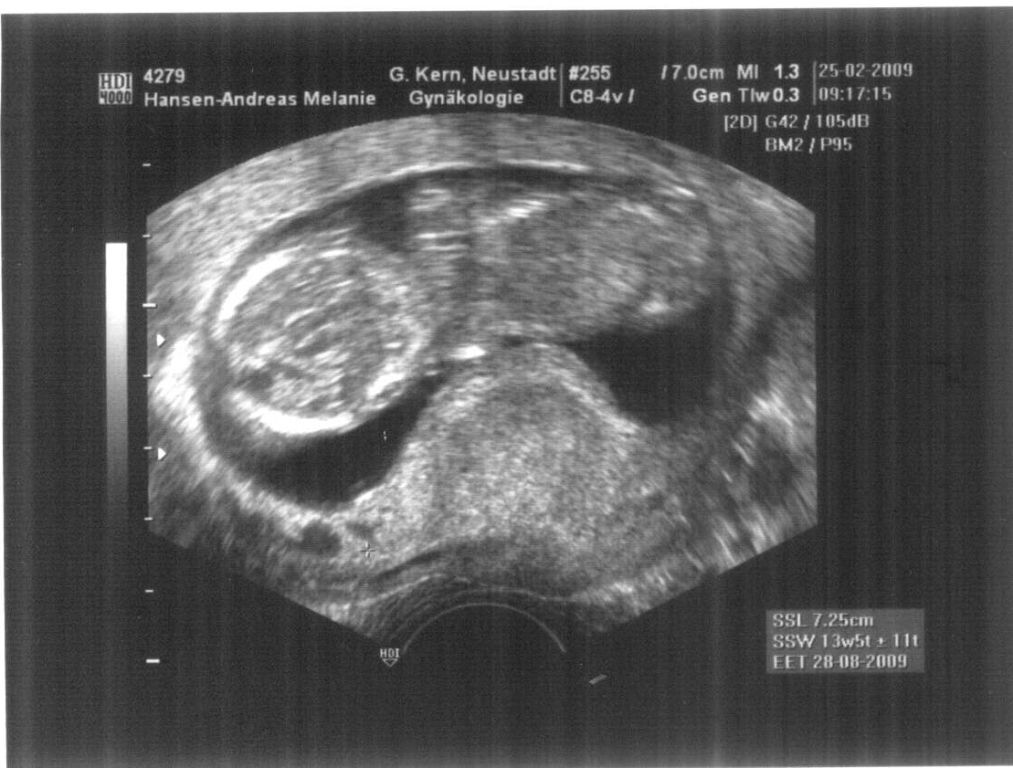

Mittwoch d. 25.02.2009: Ohje das

kann was geben. Baby geht es gut. Ist prächtig gewachsen. Aber war im

Tiefschlaf als ich bei der Untersuchung war. Die Ärztin konnte machen was

sie wollte. Baby bewegte sich keinen Meter. Ganz der Papa sag ich nur. Ein

mal am schlafen, kaum aufzuwecken. Aber Herzchen schlägt und die Größe

entspricht auch dem Stand der 14 SSW. :-D Also was will ich mehr. Meine

Werte (Blutdruck, Hämoglobin etc.) sind auch alle traumhaft. Hoffentlich

Anbei das neuste Bild unseres Schätzchens: Sieht fast aus wie das

alte.. aber baby ist Doppelt so groß.